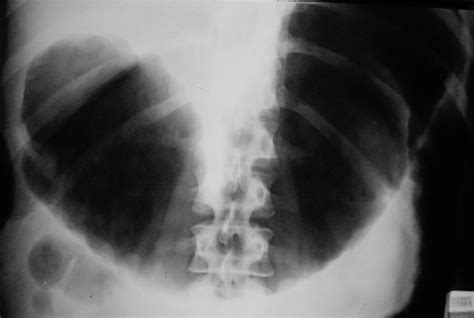

• Toxic megacolon, a life-threatening condition where the colon becomes severely dilated